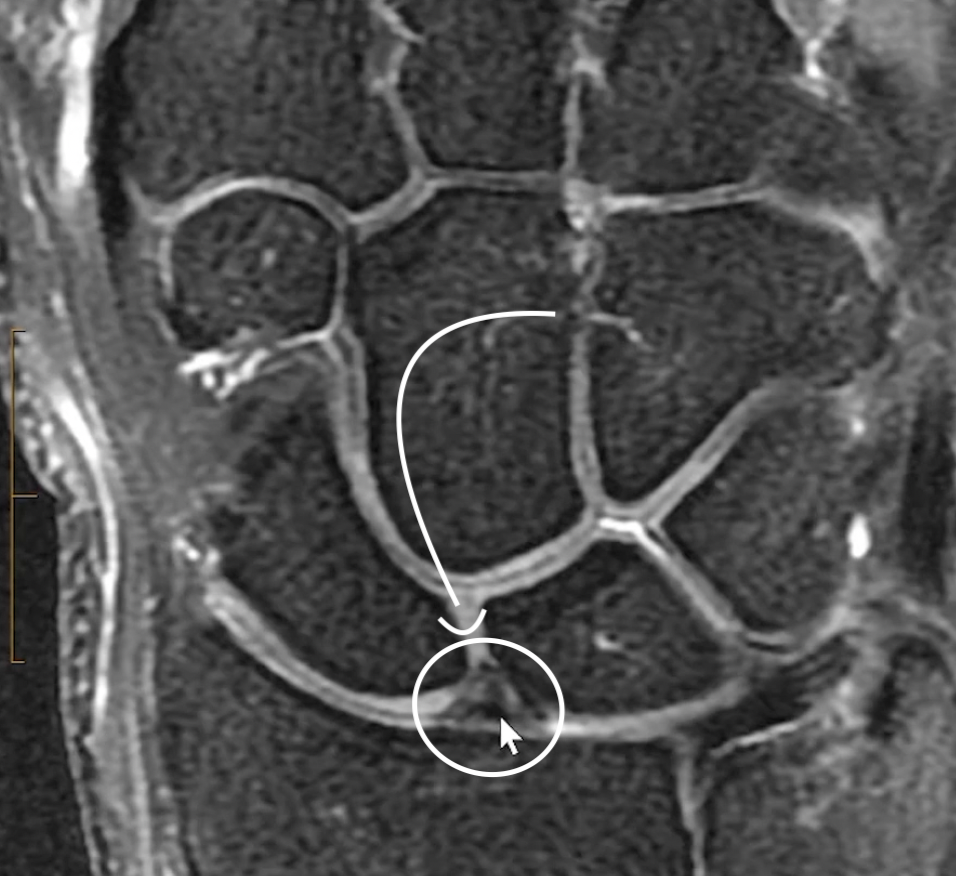

Scapholunate ligament

• Volar part (trapezoidal shaped)

• Interosseous membranous component (triangular shaped)

• Common to see signal in it and have asymptomatic tears

• Dorsal part = strongest (striated-band shaped)

Interosseous Membranous (triangle shaped)

Dorsal (striated band shaped)

Volar rhomboidal shaped